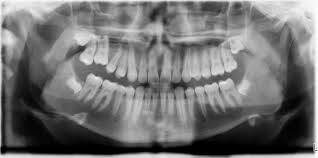

رادیوگرافی پانورامیک (O.P.G)

در رادیوگرافی‌های OPG برخلاف رادیوگرافی‌های پری آپیکال و بایت وینگ که تنها 3 یا 4 دندان مورد مطالعه قرار می‌گیرند، کلیه دندان‌های دائمی و شیری هر دو فک و استخوان فک وصورت وجود دارد. این عکس‌ها خارج از مطب دندانپزشکی، در مراکز رادیوگرافی تهیه می‌شود.

:به منظورهای زیر تهیه می‌شود OPG

1- وضعیت تکاملی جوانه‌ها دندان‌های دائمی در کودکان 6 تا 12 ساله

2- تشخیص میران نهفتگی در دندان‌های دائمی

3- مراحل تشخیص در بیماری لثه جهت جراحی

4- درمان‌های ارتودنسی